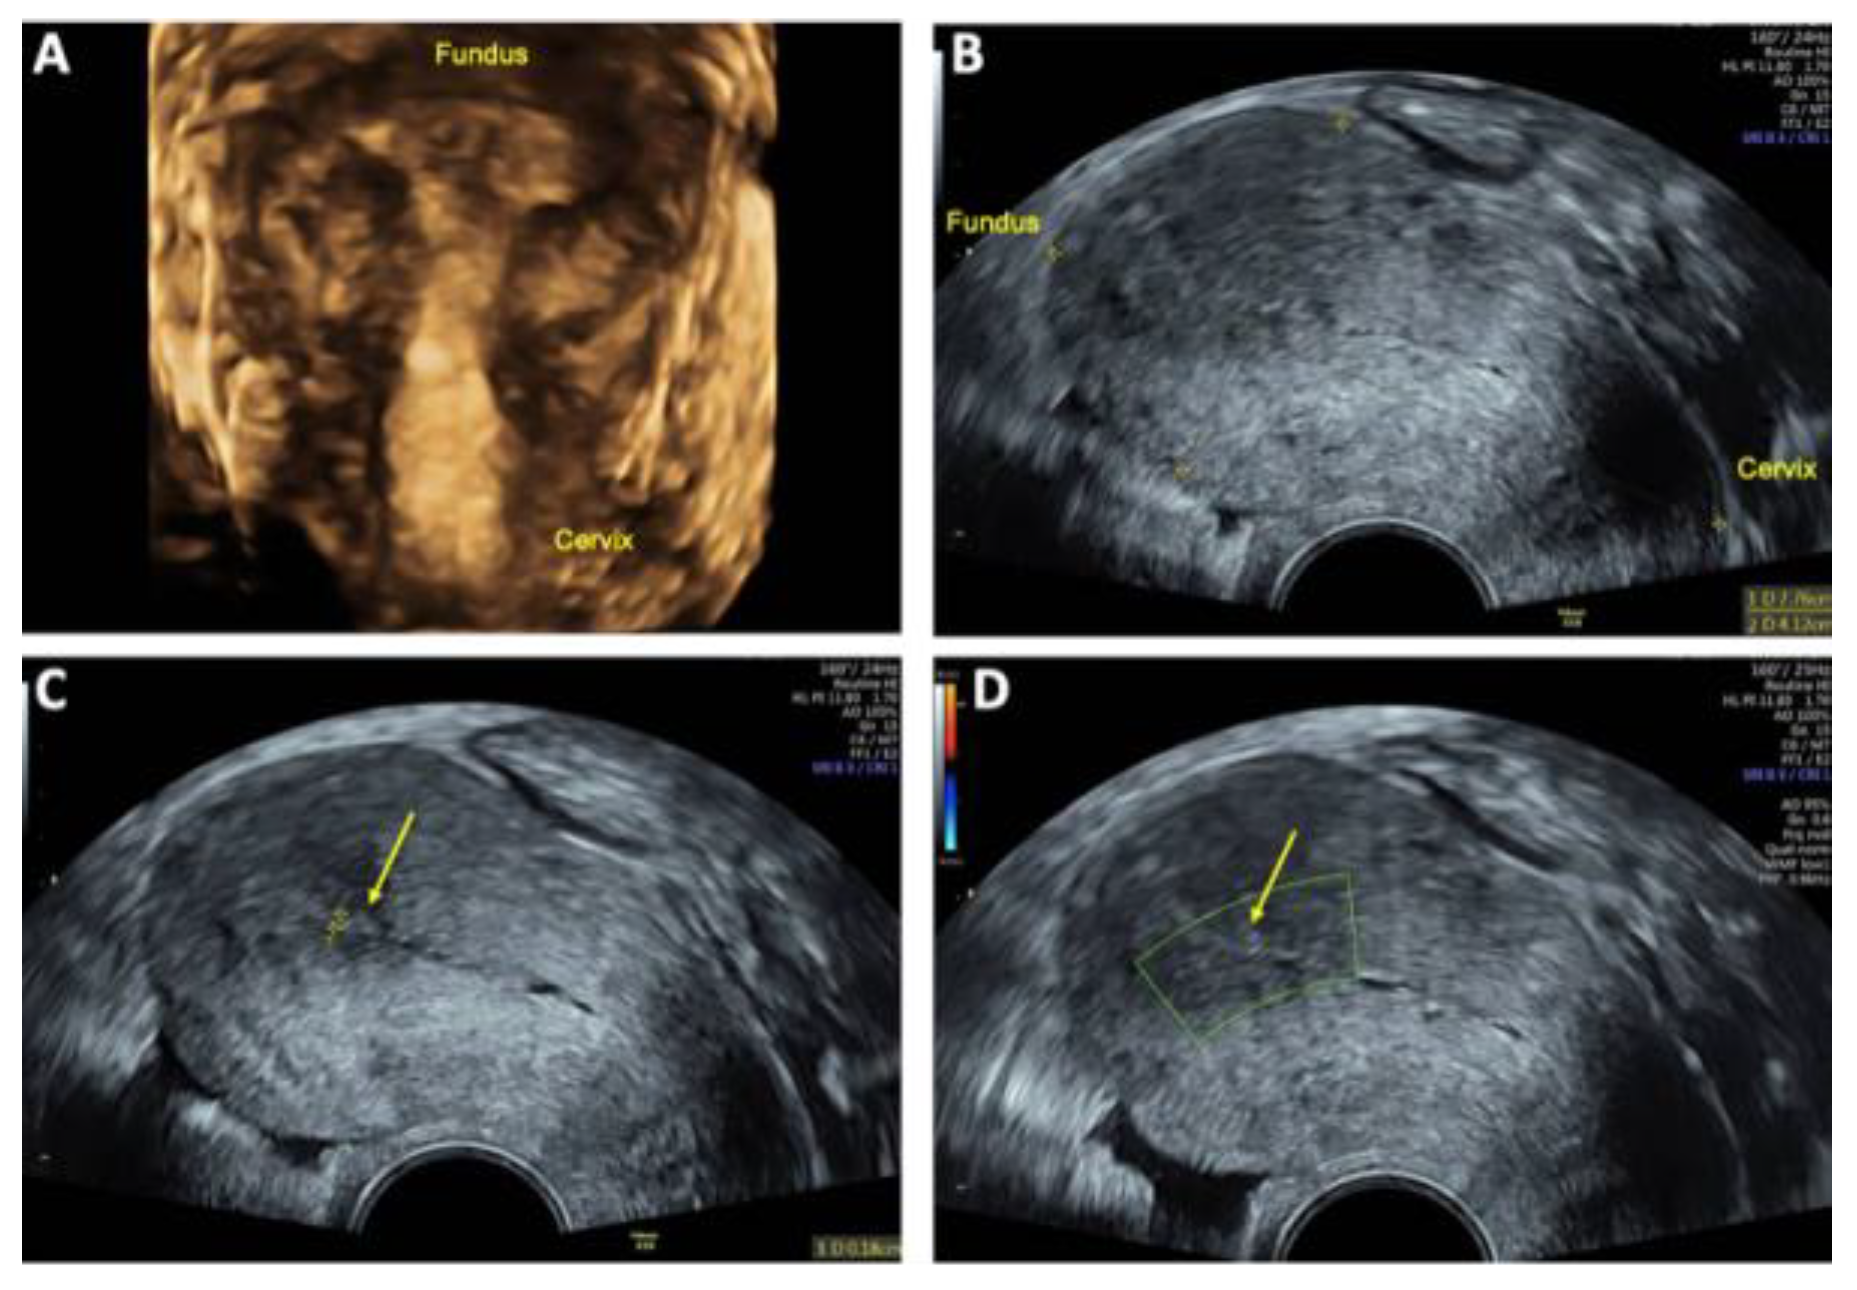

A contrast-enhanced MRI angiography scan was performed to further confirm the diagnosis. Following administration of 6 mL Gadovist®, MRI revealed a 45 × 32 mm AVM involving both the myometrium and endometrium of the left ventrolateral uterine wall, extending to the fundus. The AVM was supplied by feeding arteries from both uterine arteries, with a predominant contribution from the left uterine artery. Venous drainage was observed via the left uterine vein, further supporting the diagnosis (Figure 3).

Figure 3. Contrast-enhanced magnetic resonance imaging (MRI) of uterine arteriovenous malformation (AVM): (A) MRI angiography with Maximum intensity Projection (MIP) arterial phase demonstrating feeding arteries originating from both uterine arteries (*), with a predominant supply from the left uterine artery; (B) MRI MIP venous phase illustrating venous drainage primarily via the left uterine vein (**).